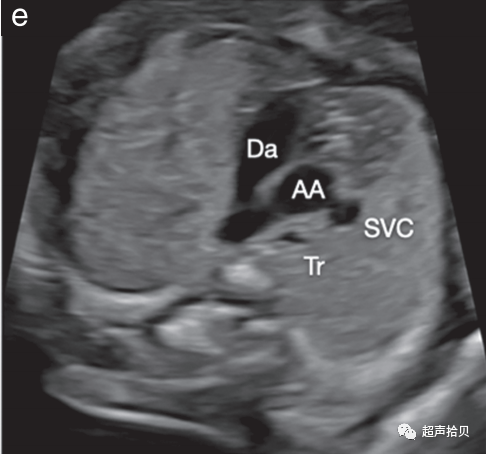

图4 用于妊娠中期胎儿心脏筛查的代表性切面。确定心脏部位,胎儿胃和胎儿心脏在同一左侧位置(未显示)。

(d)三血管切面(肺动脉(Pa)、升主动脉(Ao)和右上腔静脉(SVC))和三血管-气管切面(e)(导管弓(Da)、主动脉弓(AA)、右上腔静脉 (SVC) 和气管 (Tr)) 。

3. 三血管切面和密切相关的三血管气管切面可以改善流出道、主动脉弓和全身静脉异常的检测(图 4d、e).